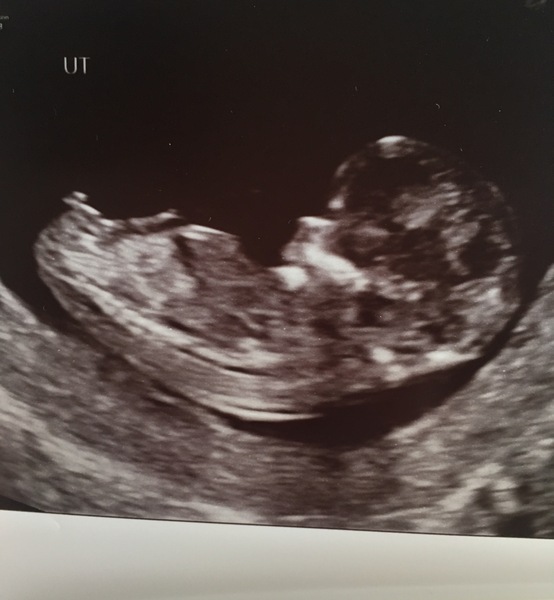

Nugget definitely didn't want to be bothered this morning, head pointing away, sonographer in my hip trying to get a good imagine, lots of hip wiggling, a lovely nugget somersault and bum shot and eventually an internal scan cuz the angle just wasn't good enough 😥 eventually got all measurements and everything looks good. Was worried cuz heartbeat looked really faint but all the activity put me at ease. EDD moved forward a day! 23rd April now! No nub to be seen unfortunately.

Congrats MissYeti! Lovely pics. And Congrats on your little boy Sam!

And hurray MissYeti! Beautiful photos, baby doing a little pout for you. Sounds like a right palaver but great that everything looked good in the end.